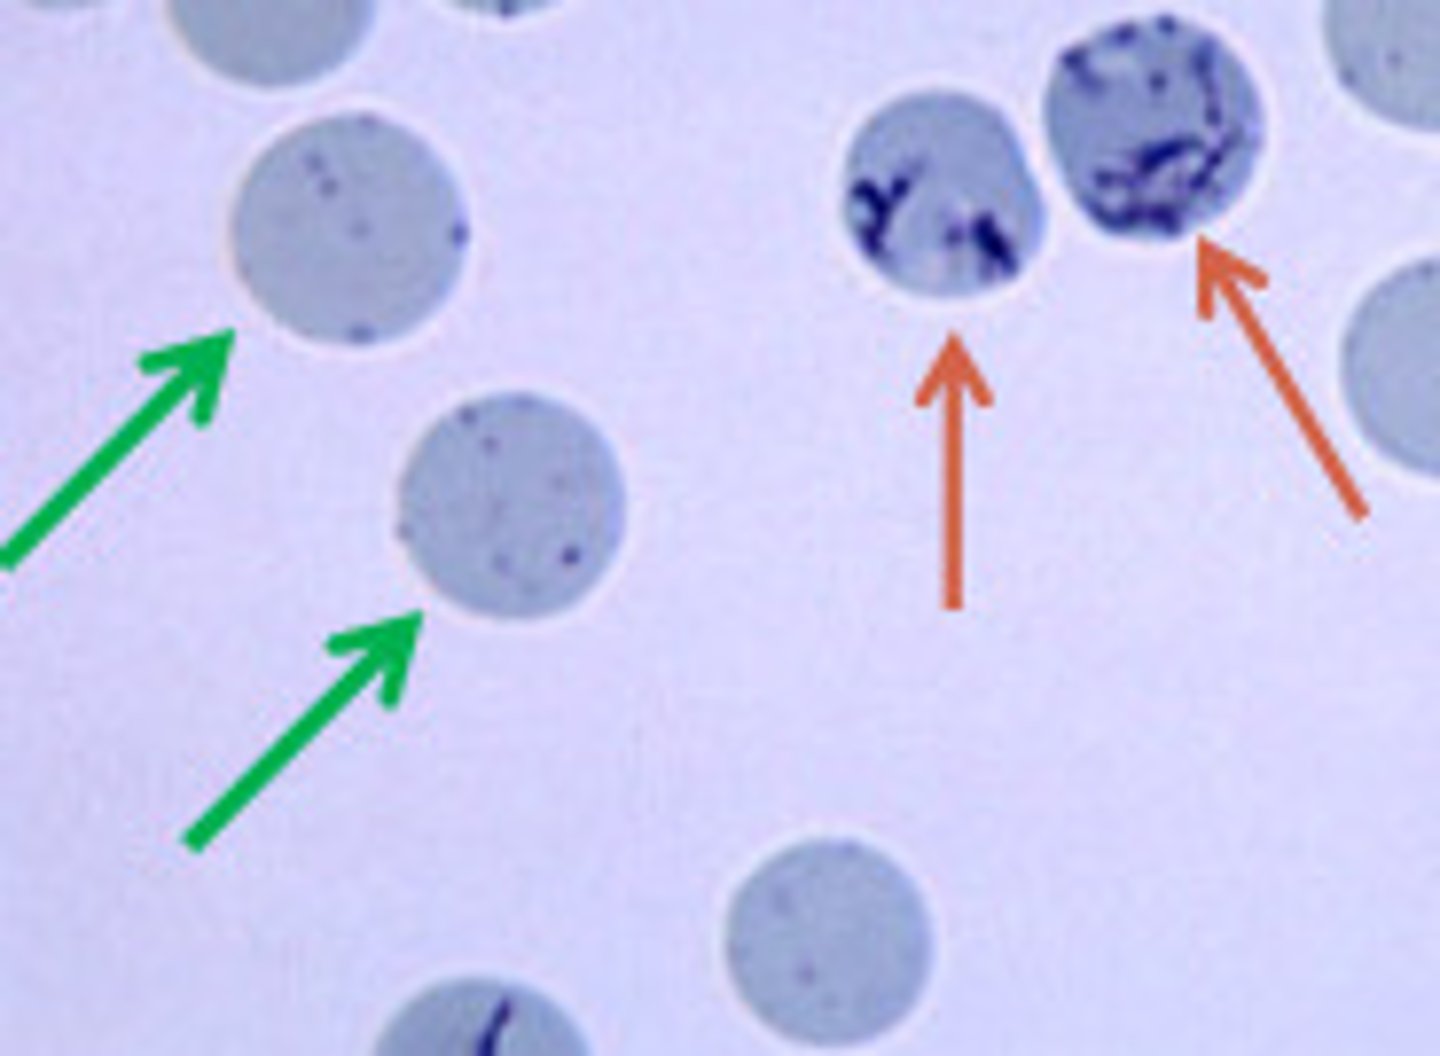

aggregate reticulocytes

orange arrow

hint: NMB stain

punctate reticulocytes

**not counted

green arrow